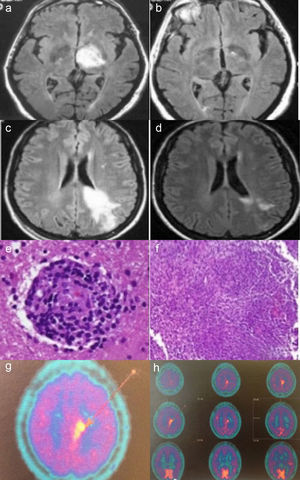

Case no. 1: Axial fluid-attenuated inversion recovery (FLAIR) magnetic resonance image (MRI) shows a hyperintense lesion in left thalamus (a). In an image acquired 2 months later, complete resolution of the lesion is observed (b). Case no. 2: Axial FLAIR MRI shows a hyperintense lesion in white matter of the left frontoparietal region, extending to the cortex and corpus callosum, in a gadolinium-enhanced image (c). MRI performed after 20 days of corticosteroid therapy shows a significant reduction in the hyperintense area (d). Histopathological findings in brain biopsy show a perivascular lymphocytic infiltrate with blood vessel involvement (hematoxylin-eosin) (e). Granulomatous inflammatory infiltrate (hematoxylin-eosin) (f). Brain 11C-methionine positron emission tomography (PET) images showing parasagittal deposition of 11C-methionine suggestive of possible lymphoma (g and h).

Case reportsCase no. 1The patient was a 63-year-old man who presented with a 1-month history of behavioral changes in the form of irritability, aggressiveness and emotional lability, as well as difficulty in walking and agraphia. He mentioned a 35-year history of recurrent oral ulcers, and that sores had appeared on his genitals over the preceding 6 months, accompanied by folliculitis in the genital region and lower extremities. In the physical examination, he was found to have temporospatial disorientation; bradypsychia; right facial, brachial and femoral paresis (4/5); and tendency to list or veer toward the right when walking; together with oral and genital ulcers. The most noteworthy laboratory findings were elevated acute phase reactant levels, negative results in serological tests for Brucella, syphilis, hepatitis B virus, hepatitis C virus and human immunodeficiency virus, and negative findings in an autoimmunity study. He tested positive for HLA B51. Brain magnetic resonance imaging (MRI) revealed the presence of a space-occupying lesion in left thalamus (Fig. 1.1). An angiographic study of the supra-aortic trunks revealed small-vessel disease and atheromatous lesions in the carotid bifurcations, as well as saccular aneurysms and infundibula, with images of vascular nidi in the left carotid territory suggestive of vasculitis. Thoracoabdominal computed tomography was normal. Lumbar puncture yielded clear cerebrospinal fluid, with an unremarkable protein content, without oligoclonal bands. As NBD was suspected, treatment was initiated with methylprednisolone pulse therapy, followed by oral prednisone (1mg/kg body weight [bw]/day), colchicine (1mg/12h) and oral azathioprine (2mg/kg bw/day). The patient's clinical status improved, his genital ulcers disappeared and there was no evidence of the neurological manifestations. After 3 months of treatment, he underwent follow-up brain MRI which revealed the complete resolution of the lesion (Fig.1.2). After 15 years of follow-up, the patient has no clinical neurological symptoms and is receiving absolutely no treatment. However, he has had sporadic oral aphthae, which have responded well to colchicine.

The second patient was a 35-year-old woman who had generalized seizures and a 2-month history of paresthesia in the right malar region. The results of the physical examination were normal. Laboratory analyses showed elevated acute phase reactant levels, negative results in serological tests for human immunodeficiency virus, hepatitis B virus and hepatitis C virus, and a negative autoimmunity study. Brain MRI revealed the presence of an intraparenchymal infiltrative lesion affecting left frontoparietal region, with enhanced images following gadolinium administration (Fig. 1.3), which was diagnosed as a brain tumor. Lumbar puncture yielded clear, acellular fluid with slightly elevated protein content and no oligoclonal bands. Treatment was begun with intravenous dexamethasone (12mg/day), which was subsequently tapered. Twenty days later, brain MRI showed a significant reduction in the size of the lesion (Fig. 1.4). 11C-methionine positron emission tomography (PET) of the brain suggested the presence of cerebral lymphoma (Figs. 1.7 and 1.8). The brain mass was biopsied, and the histological study revealed the presence of a focal necrotizing granulomatous infiltrate with lymphocytic vasculitis (Figs. 1.5 and 1.6). Ziehl-Neelsen, periodic acid Schiff (PAS) and silver stains were negative. The results of thoracoabdominal computed tomography, 67gallium scintigraphy and a transbronchial biopsy ruled out sarcoidosis. Three months later, the patient developed oral and genital ulcers. She tested positive for HLA B51. With findings indicative of NBD, treatment was begun with monthly cyclophosphamide pulses (1g/month) plus tapering glucocorticoid doses. After 5 months with this treatment, she had another seizure, and brain MRI performed at that time showed that the lesion had increased in size. As cyclophosphamide was considered to be ineffective, it was replaced by oral azathioprine (2mg/kg bw/day) and the prednisone dose was increased to 30mg/day, after which it was tapered. Four months later, there was no evidence of improvement in the lesion on brain MRI, and the decision was made to start treatment with intravenous infliximab (3mg/kg bw every 8 weeks). After 8 doses of infliximab, there was a significant reduction in the size of the mass, but the patient developed diffuse joint pain and refused to continue the treatment. It was replaced by adalimumab, which she tolerated well. At the time of this writing, 5 years later, she continues to receive subcutaneous adalimumab (40mg/15 days) as single-drug therapy. Her tolerance is well and the brain lesion has not progressed. Over the course of the disease, she has had episodes of oral ulcers that responded to symptomatic treatment.